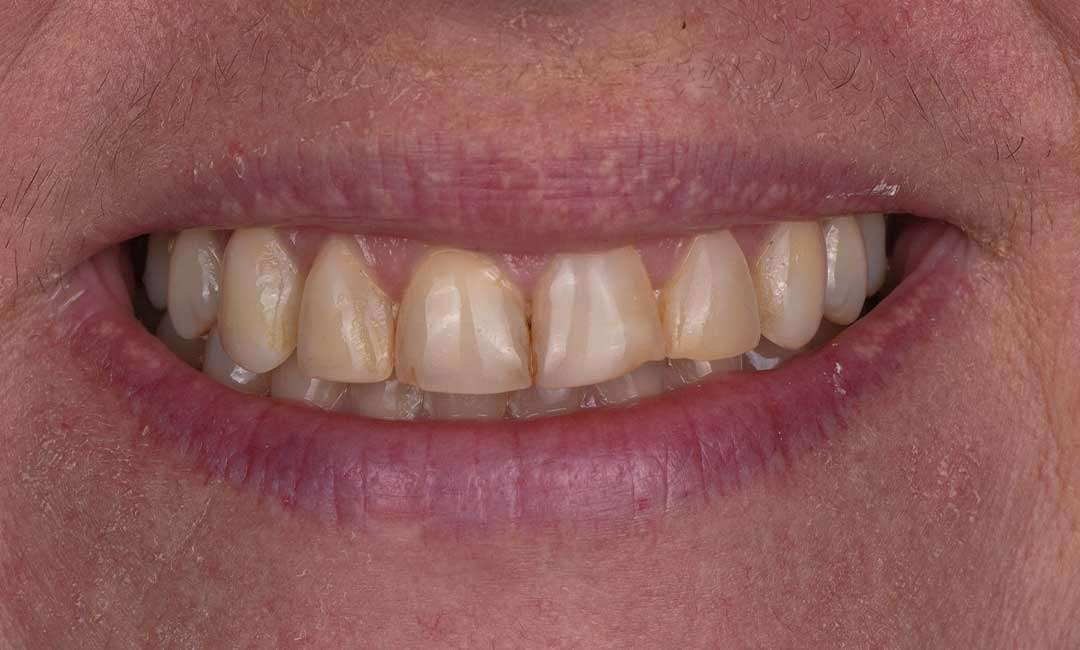

Before

Before And After Full MouthRehabilitation Treatment